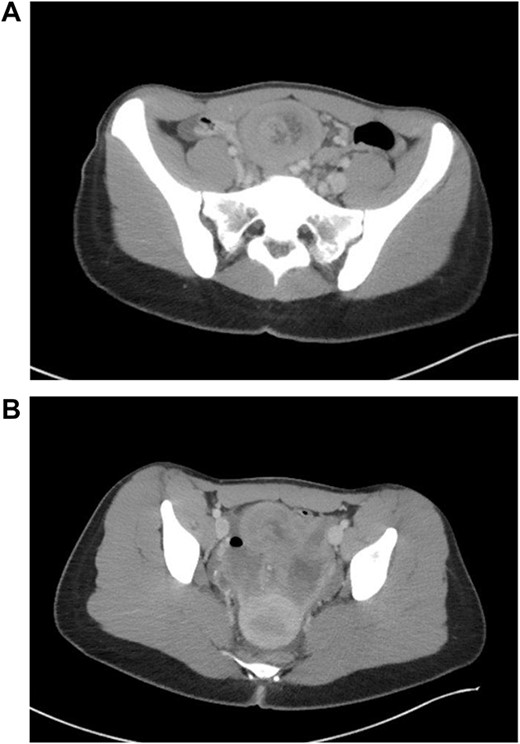

The patient developed abdominal pain with associated leukocytosis with left shift, which prompted a CT of the abdomen and pelvis on postop Day 4 with evidence of moderate to large amount of ascites and a large amount of scattered pneumoperitoneum (Fig. 2).

CT imaging with evidence of ascites and scattered pneumoperitoneum.